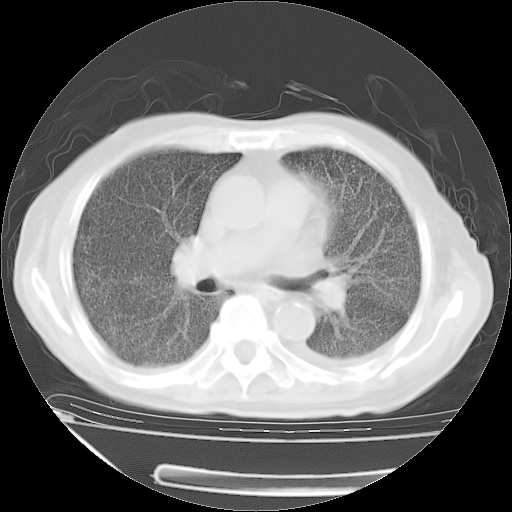

经过24天治疗,岳父的病情基本稳定。生活基本可以自理,可以下床活动。呼吸困难早已消失。体温基本正常。

只是甲强龙用80mg时血小板升到正常,改为60mg后又降到63×10*9/L。

主要治疗甲强龙80mg×14天,60mg×10天;同时抗结核(异烟肼+利福平+乙胺丁醇)。环磷酰胺0.1 tid 10天。

特别感谢胡教授、高管、桃子版主给出关键的治疗建议。桃版把所有肺部影像和全部临床资料请所在医院呼吸科、感染病科、结核科、临床免疫科专家会诊。临床免疫科专家制定了完整的治疗方案。

下一步治疗强地松+环磷酰胺+抗结核。 |